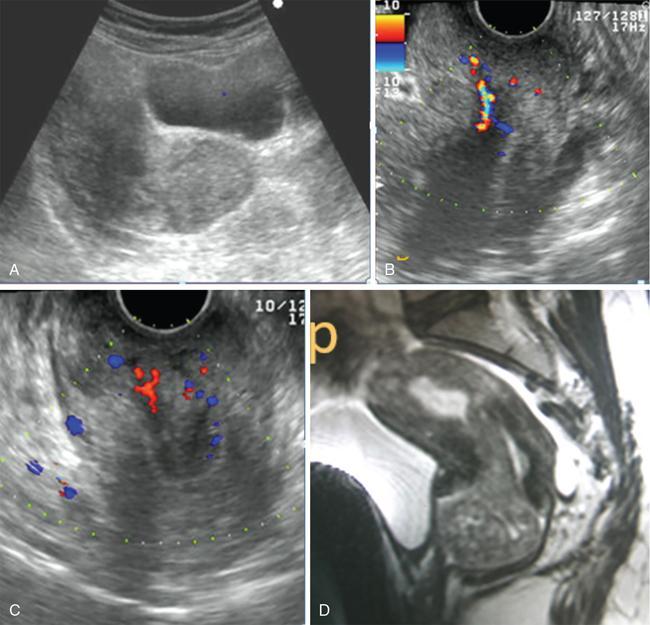

John De Lindsay, Usha Nandini Ganeshan, Vidya CERVICITIS Acute or chronic inflammation of cervix is termed as cervicitis. Noninfectious causes of cervicitis include trauma, pelvic radiation and chemical irritation. Most acute cervicitis is secondary to an infectious agent, commonly Trichomonas vaginalis, Candida albicans, herpes simplex virus, Neisseria gonorrhoeae and Chlamydia trachomatis. Patients usually present with purulent or mucopurulent cervical and vaginal discharge and may complain of pelvic pressure or discomfort. The cervix in patients with acute cervicitis shows a diffusely heterogeneous echotexture of the cervical mucosa and stroma, but the key finding is markedly increased vascularity on colour Doppler. Absence of mass is the differentiating feature between inflammation and malignancy. Free fluid can also be seen in the pouch of Douglas. CT may demonstrate an enlarged uterine cervix, an abnormally enhancing endocervical canal, and parametrial fat stranding. Retention cysts of the uterine cervix are termed as nabothian cysts. They are formed as a result of the healing process of chronic cervicitis. They are usually less than 1 cm, incidentally detected at imaging and are considered a normal finding in multiparous women. They may enlarge and become symptomatic because of mass effect, but this happens infrequently Majority of nabothian cysts, appear as small, simple anechoic cysts in the cervix, with no internal vascularity (Fig. 11.18.1.1). Their appearances can also vary depending upon any internal proteinaceous or haemorrhagic content, cyst clustering and deeper cervical stromal extension. US features that raise concern for malignancy include a solid component and marked vascular flow in the lesion at colour Doppler US. Tunnel cluster is a special variant of nabothian cyst with complex multicystic dilatation of the endocervical glands. Though macroscopically it resembles adenoma malignum, the epithelial cells of the tunnel cluster, do not show any cellular atypia similar to nabothian cyst. Nabothian cysts exhibit intermediate or slightly high signal intensity on T1-weighted (T1W) images and have prominent high signal intensity on T2-weighted (T2W) images. Presence of a solid component surrounding or separating the cysts gives us a clue to differentiate adenoma malignum from a benign nabothian cyst cluster. MR imaging also may be helpful in distinguishing adenoma malignum from benign multicystic lesions of the cervix. MR imaging features associated with malignancy include irregular margins, enhancing solid components, local invasion and metastases. CERVICAL STENOSIS Stenosis of the uterine cervix is the pathological narrowing of the cervix. The term cervical stenosis is clinically defined as cervical narrowing that prevents the insertion of a 2.5-mm-wide dilator. In utero exposure to diethylstilbestrol contributes about 20% of the cases. Often associated with endometriosis. Cervical stenosis in menopausal patient is asymptomatic. Retrograde menses may occur in women of reproductive age, thus posing a risk of endometriosis. Dysmenorrhea is present in up to 50% of patients with cervical stenosis. If the stenosis is severe enough, it may result in proximal obstruction resulting in haematometra, hydrometra, pyometra, haematosalpinges. The symptoms depend upon the severity of stenosis. Other potential consequences include infertility, impediment to assisted fertility techniques – embryo transfer and intrauterine insemination. Any pathological process that can cause inflammation of the cervical mucosa, resulting in erosion and regeneration can result in cervical stenosis. This includes: Narrowing of the endocervical canal may be observed (normal diameter: 0.5–3.0 cm). Complete obliteration of the cervical os will prevent insertion of the hysterosalpingographic catheter. The endocervix can be normal in appearance or slightly thickened. If post irradiation, the cervix may demonstrate loss of the normal zonal architecture. There may be mild to moderate fluid distension of the endometrial cavity (Fig. 11.18.2.1). If the fluid has internal echoes a careful search for potentially associated endometrial or cervical mass lesions, should be done. Complex, particulate intracavitatory fluid with its heterogeneous echogenicity at ultrasound may mimic a solid lesion; however, the absence of detectable flow at colour Doppler US and the central location should suggest the correct diagnosis. May reveal complications due to cervical stenosis such as hydrometra and haematometra and haematosalpinges. Though the cervix may be appear normal, the uterine cavity may be fluid filled. Auxiliary findings may suggest an underlying cause, such as an obstructive mass lesion, or post radiation bowel wall thickening. In equivocal cases, MR imaging may be useful to differentiate complex endocervical fluid from a mass. In selected situations, gradual dilatation of the cervix under ultrasound guidance, can be an effective treatment. Depending on severity of disease, other treatment options include insertion of laminaria tent, hysteroscopic cervical excision or in extreme cases total hysterectomy. CERVICAL POLYPS The common cervical polyps are prolapsing endometrial polyps. They are seen in endocervial canal. Endometrial polyps are common and a frequent cause of abnormal uterine bleeding. They account for approximately 30% of cases of postmenopausal bleeding. In menstruating females, they may cause intermenstrual bleeding, metrorrhagia, and infertility. Polyps can be histologically characterized as localized hyperplastic overgrowths of glands and stroma covered by epithelium. The typical appearance of an endometrial polyp at sonography is a well-defined, homogeneous, polypoid lesion that is isoechoic to hyperechoic to the endometrium with preservation of the endomyometrial interface (Fig. 11.18.3.1). There usually is a well-defined vascular pedicle within the stalk demonstrated on colour Doppler sonography (Fig. 11.18.3.2). Uncommon features of polyps include multiplicity, cystic components, a broad base and hypoechogenicity or heterogeneity. Occasionally, polyps can have a heterogeneous echotexture with multiple cysts. This complex appearance may be due to haemorrhage, infarction or inflammation within the polyp. Sonohysterography is an ultrasound technique in which the endometrial cavity is distended with saline allows evaluation of single layer of the endometrial lining and enables us to reliably distinguish focal from diffuse endometrial pathologic conditions. Focal lesions are defined as lesions occupying less than 25% of the endometrial surface area and diffuse lesions involve a larger percentage of the endometrial surface area. Saline infusion sonohysterography which involves the infusion of fluid to visualize the endometrium is a simple, well-tolerated and inexpensive procedure. Sonohysterography is best performed as soon as possible after the bleeding cycle has ended when the endometrium is thin. When the patient has irregular bleeding, that she cannot tell what is actual menses, in such cases it may be helpful to use an empiric course of a progestogen such as medroxyprogesterone acetate 10 mg daily for 10 days as a medical curettage and then time the ultrasound examination to the withdrawal bleed. The decision about whether to obtain cultures and use of antibiotics depends very much on the patient population with which the physician deals with. Anaesthesia or analgesia is not required. A bimanual examination to know the version of the uterus is done. The vaginal speculum is inserted. Under sterile aseptic precautions, a catheter is inserted into the cervix. This is done by grasping the cervix with a ring forceps feeding it through the os. A cervical stabilizer may be used and it will be less painful, less traumatic and does not cause bleeding from the cervix. The speculum is removed without dislodging the catheter. The vaginal probe is then reinserted. A 10-mL syringe is attached to catheter. Scanning in long-axis projection, fluid is instilled while watching the video monitor. In that long-axis projection the transducer is removed from side to side (i.e. from cornua to cornua). The amount of fluid instilled is variable and depends on the image which is producing on the ultrasound screen. When the uterus has been completely rotated 90 degrees into a coronal plane further fluid is instilled, while fanning down toward the endocervical canal and up toward the uterine fundus. Very minimal fluid acts as a sufficient interface to distinguish anterior and posterior endometrial surfaces and outline endometrial pathology. The risk of malignant cell dissemination exists but is small. The saline infusion sonohysterography can reliably distinguish dysfunctional abnormal bleeding (no anatomic abnormality) from those with globally thickened endometrium. Endometrial polyp appears as homogeneous, well-circumscribed, polypoid lesion that is isoechoic to the endometrium with preservation of endometrial–myometrial interface. Other features can be cystic components, multiplicity, a broad base, and hypoechogenicity or heterogeneity. Submucosal leiomyomas are usually broad-based, hypoechoic, well-defined, solid masses with shadowing and an overlying layer of echogenic endometrium that distorts the endometrial–myometrial interface. They are pedunculated or have a multilobulated surface. The major advantage of sonohysterography is the accuracy in depicting the percentage of the fibroid that projects into the endometrial cavity. In contrast to the transvaginal US demonstration of polyps, which may distort measurements of endometrial thickness if made before saline infusion, at sonohysterography the uninvolved single-layer endometrium appears normal in thickness and should be measured separately from the polyp. The findings at sonohysterography determine whether a blind biopsy, hysteroscopically guided biopsy, or hysteroscopically guided dilation and curettage is the appropriate diagnostic. On MRI polyps appear T2 isointense to hypointense and demonstrate postcontrast enhancement (Fig. 11.18.3.3). Polyps generally enhance less than the surrounding endometrium but more than myometrium. Most of endometrial polyps can be reliably differentiated from submucosal leiomyomas on MR imaging with leiomyomas having hypointense signal on T2W and visualizing origin from the myometrium. A small percentage of endometrial polyps may contain malignant foci or foci of endometrial hyperplasia. Hormones (endogenous or exogenous), tamoxifen usage, nulliparity, obesity, hypertension and diabetes. Histologic patterns of endometrial hyperplasia vary from hyperplasia without atypia, which has little or no malignant potential, to severe atypia in which 20% of cases progress to endometrial cancer. Endometrial hyperplasia accounts for approximately 4%–8% of cases of postmenopausal bleeding. In sonohysterography, endometrial hyperplasia appears as a diffuse thickening of echogenic endometrial stripe without focal abnormality, uncommonly focal endometrial hyperplasia can be seen. In sonohysterography the latter form of hyperplasia is more difficult to differentiate from endometrial polyps because characteristics of the focal endometrial thickening in both conditions overlap. Endometrial cancer is typically a diffuse process, but early cases can appear as a polypoid mass. Imaging features of endometrial hyperplasia include irregular thickening of the endometrium with T2 hyperintensity compared to normal myometrium and T1 hypointensity relative to myometrium on early contrast-enhanced images. Endometrial thickening measuring >5 mm in postmenopausal females with bleeding, regardless of hormonal therapy should undergo further investigation including tissue sampling to exclude endometrial cancer. Cervical polyps are the commonest causes of intermenstrual vaginal bleeding. Most patients are perimenopausal present with symptoms including menorrhagia, postmenopausal bleeding, contact bleeding and vaginal discharge. Pathologic conditions of cervical polypoid lesions include endometrial or endocervical tissue with metaplasia, leiomyoma, inflammation or malignancy or even blood clot. Most common are endocervical polyp, account for more than 60% of cervical polypoid lesions. More commonly polyps are pedunculated, with a slender pedicle of varying length, but few are sessile. The diagnosis is made primarily with hysteroscopy. Endocervical polyps are usually seen as masses with or without cysts filling endocervical or vaginal canal. Identifying the stalk attaching to the cervical wall may differentiate it from endometrial polyp. On USG it appears hypoechoic or echogenic with a stalk. CERVICAL CARCINOMA Cervical carcinoma is the third most common gynaecological malignancy after endometrial and ovarian malignancies. It affects middle-aged females from 35 to 50 years with an average age of onset at around 45 years. It is one of the leading causes of deaths among women in developing countries. Prognosis depends on tumour size, nodal status, histological grading and staging at the time of diagnosis. So accurate staging of the disease is very important to decide the treatment strategy.